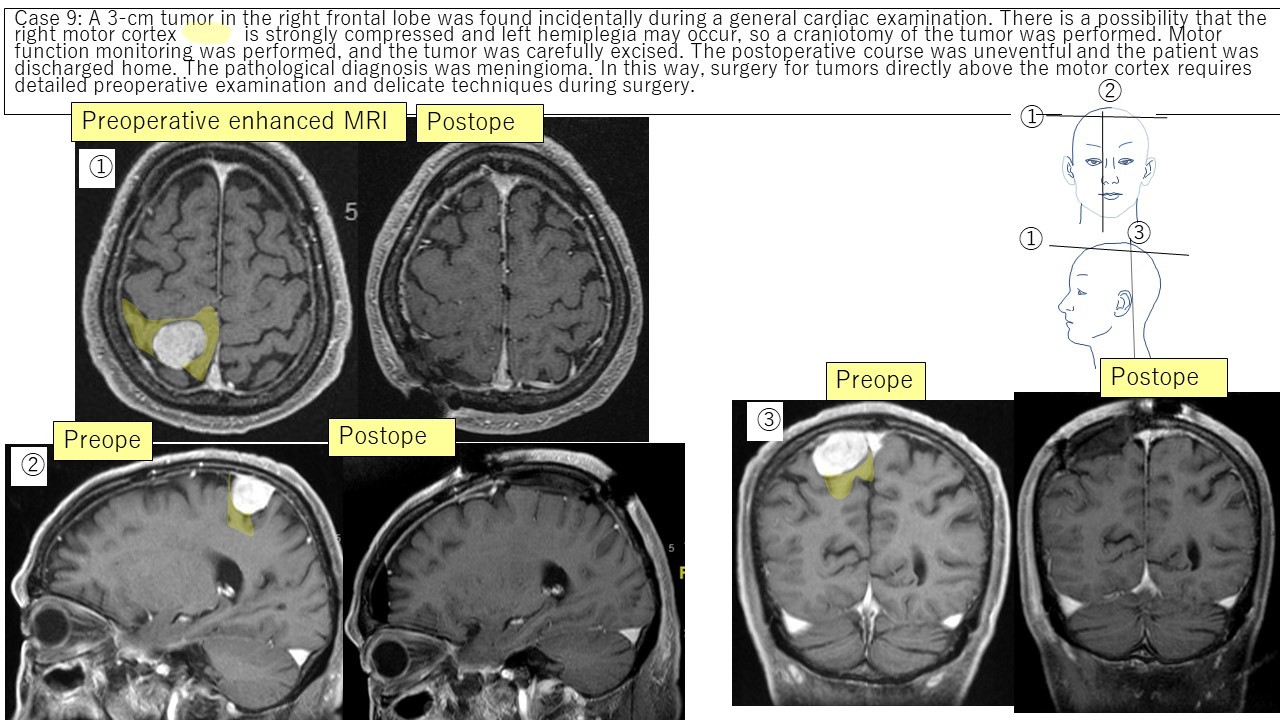

Parasagittal meningioma Case 8 Case 9 Case 10